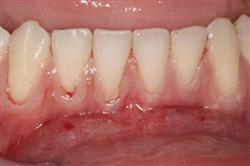

Normally gum tissue surrounds and protects the delicate roots of your teeth. Exposed tooth roots are prone to tooth decay, root canals, discoloration and actual jawbone loss. All of this can lead to tooth loss in advanced cases.

Functional Soft Tissue Grafting replaces the missing gum tissue and protects your teeth. For this reason, soft tissue grafting may be recommended even for back teeth.